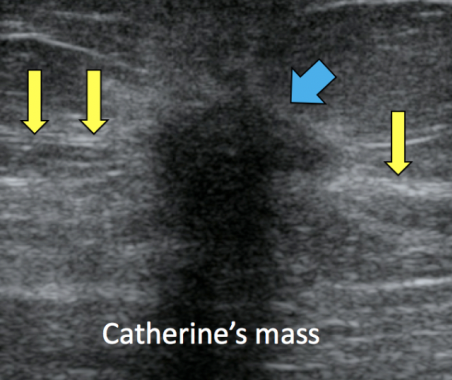

Solid mass

(as on USS; solid tissue appears as varying shaded of grey)

Malignant mass

benign mass because: